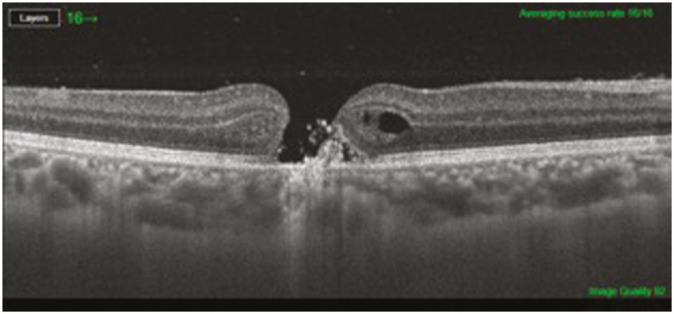

一名 25 岁的美容师正在操作波长为 1,064 nm 的 Q 开关脉冲(SPECTRA)美容激光机进行皮肤漂白。探头突然滑过为避免 COVID-19 暴露而放置的塑料布,随后她抱怨视力突然下降。她被诊断为右眼玻璃体出血,接受了一个月的保守治疗。之后,她主诉出现中心视力障碍,并被诊断为黄斑全厚孔,医生建议她进行玻璃体切除手术。本病例报告旨在强调在 COVID-19 时代采取预防措施的重要性,同时要确保如何操作机器,以免对手术医生造成任何意外伤害。使用 Nd:YAG 激光漂白皮肤后,在操作美容师身上出现的黄斑孔与在患者身上出现的黄斑孔相比非常罕见。

A 25-year-old aesthetician was operating Q-switch pulse (SPECTRA) cosmetic laser machine of 1,064 nm wavelength, for the purpose of skin bleaching. The probe suddenly slipped over the plastic sheet that had been placed to avoid COVID-19 exposure after which she complained of sudden loss of vision. She was diagnosed as having vitreous hemorrhage in her right eye and was treated conservatively for one month. She then complained of central scotoma and was diagnosed to have developed a full-thickness macular hole, for which she was advised vitrectomy surgery. The purpose of this case report is to emphasize the importance of taking precautions during the COVID-19 era and while doing that making sure how to handle the machines so as not to inflict any accidental injury to the operating physician. Macular Holes following skin bleaching with Nd:YAG laser occurring in operating aesthetician is rare as compared to that occurring in the patients.